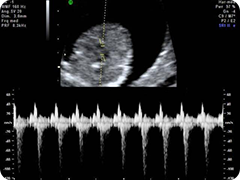

La translucenza nucale (NT) è un esame ecografico di screening che viene offerto di routine a tutte le donne in stato di gravidanza, con lo scopo di selezionare le pazienti maggiormente esposte al rischio di avere un figlio affetto da Sindrome di Down. Tale sindrome rappresenta l’anomalia cromosomica di più frequente riscontro con una prevalenza della malattia di circa 1 caso su 600 nati vivi. Ogni donna gravida presenta un certo rischio di partorire un bambino affetto dalla malattia con una percentuale di rischio che aumenta con l’avanzare dell’età materna. Tuttavia, anche se in percentuale molto bassa, tale rischio esiste anche nelle donne giovani. Poiché il criterio dell’età materna consente di identificare soltanto il 30% dei feti affetti da anomalie cromosomiche, si è reso necessario individuare altri parametri che potessero aumentare la capacità di selezionare le pazienti maggiormente a rischio. La NT consiste nella misura ecografica di in una raccolta di liquido sottocutaneo nella regione cervicale del feto che in caso di sindrome di Down è superiore alla media. Tuttavia non tutti i feti Down hanno una NT aumentata e, al contrario, alcuni feti normali hanno una NT alterata; pertanto esistono sia falsi positivi che falsi negativi. Accettando una percentuale di falsi positivi del 5%, la sensibilità della NT (cioè la capacità di riconoscere un feto Down) è del 75-80%. Associando alla NT il dosaggio di alcuni marcatori biochimici sul sangue materno (free-beta HCG e PAPP-A) si raggiunge un affidabilità tre volte superiore al parametro dell’età materna con una sensibilità pari al 90%. Esecuzione: La misura della translucenza nucale viene effettuata in un’epoca di gravidanza compresa tra 11 e 14 settimane di gestazione. Se è stato richiesto il test combinato (cosa consigliata vista la maggiore sensibilità), prima di effettuare l’ecografia viene eseguito un prelievo di sangue per il dosaggio di free-beta HCG e PAPP-A. L’ecografia viene eseguita per via addominale; alcune volte è necessario attendere che il feto cambi la sua posizione per consentire una corretta misurazione; eccezionalmente è necessario il ricorso alla via transvaginale in caso di posizione costantemente sfavorevole del feto. La tecnica di misurazione deve rispettare dei criteri standard ben definiti che garantiscono l’accuratezza dello screening . Alla misura della NT si può aggiunger la ricerca di markers supplementari quali l’osso nasale, il flusso nel dotto venoso, l’angolo maxillo-facciale e il rigurgito tricuspidalico. La capacità manuale dell’operatore, confortata dall’impiego di apparecchiature sempre più sofisticate, consente inoltre di approfondire l’esame ecografico con una valutazione morfologica che permette di evidenziare vari ed importanti dettagli anatomici del feto e di riconoscere molto precocemente alcune malformazioni fetali. Risultati: I dati relativi alla misura della translucenza nucale, alle dimensioni del feto, all’età materna ed alla concentrazione nel sangue materno dei marcatori biochimici (free-beta HCG e PAPP-A) vengono inseriti in un software, in dotazione esclusiva al medico accreditato, che sviluppa la stima del rischio per Sindrome di Down. I risultati dei marcatori sono pronti in circa tre ore dalla effettuazione del prelievo, per cui l’esito definitivo del test combinato viene consegnato alla paziente nella stessa giornata; nel caso la paziente non voglia attendere in studio, la risposta definitiva le viene comunicata telefonicamente e il risultato inviato per posta. Il valore di rischio al di sopra del quale si consiglia la villocentesi o l’amniocentesi è di 1/300 e lo si riscontra nel 5% dei casi esaminati. Quando il test risulta positivo per una translucenza nucale aumentata o per valori biochimici alterati o per entrambe le condizioni, questo non significa che il feto è necessariamente affetto dalla cromosomopatia, ma solo che il suo rischio è aumentato e pertanto è opportuno procedere ad una indagine diagnostica invasiva. Un test negativo (rischio inferiore a 1/300) significa invece che il rischio della paziente di avere un bambino Down è inferiore a quello atteso in base alla sola età, per cui non c’è indicazione clinica alla diagnosi prenatale invasiva. |